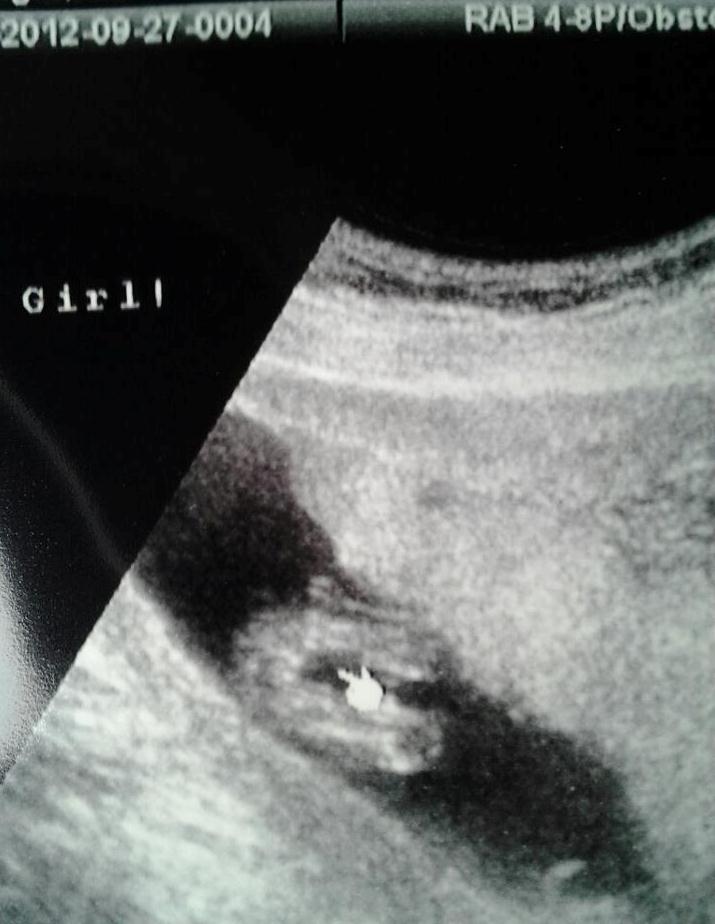

And then 14 weeks:

Attachment 5191